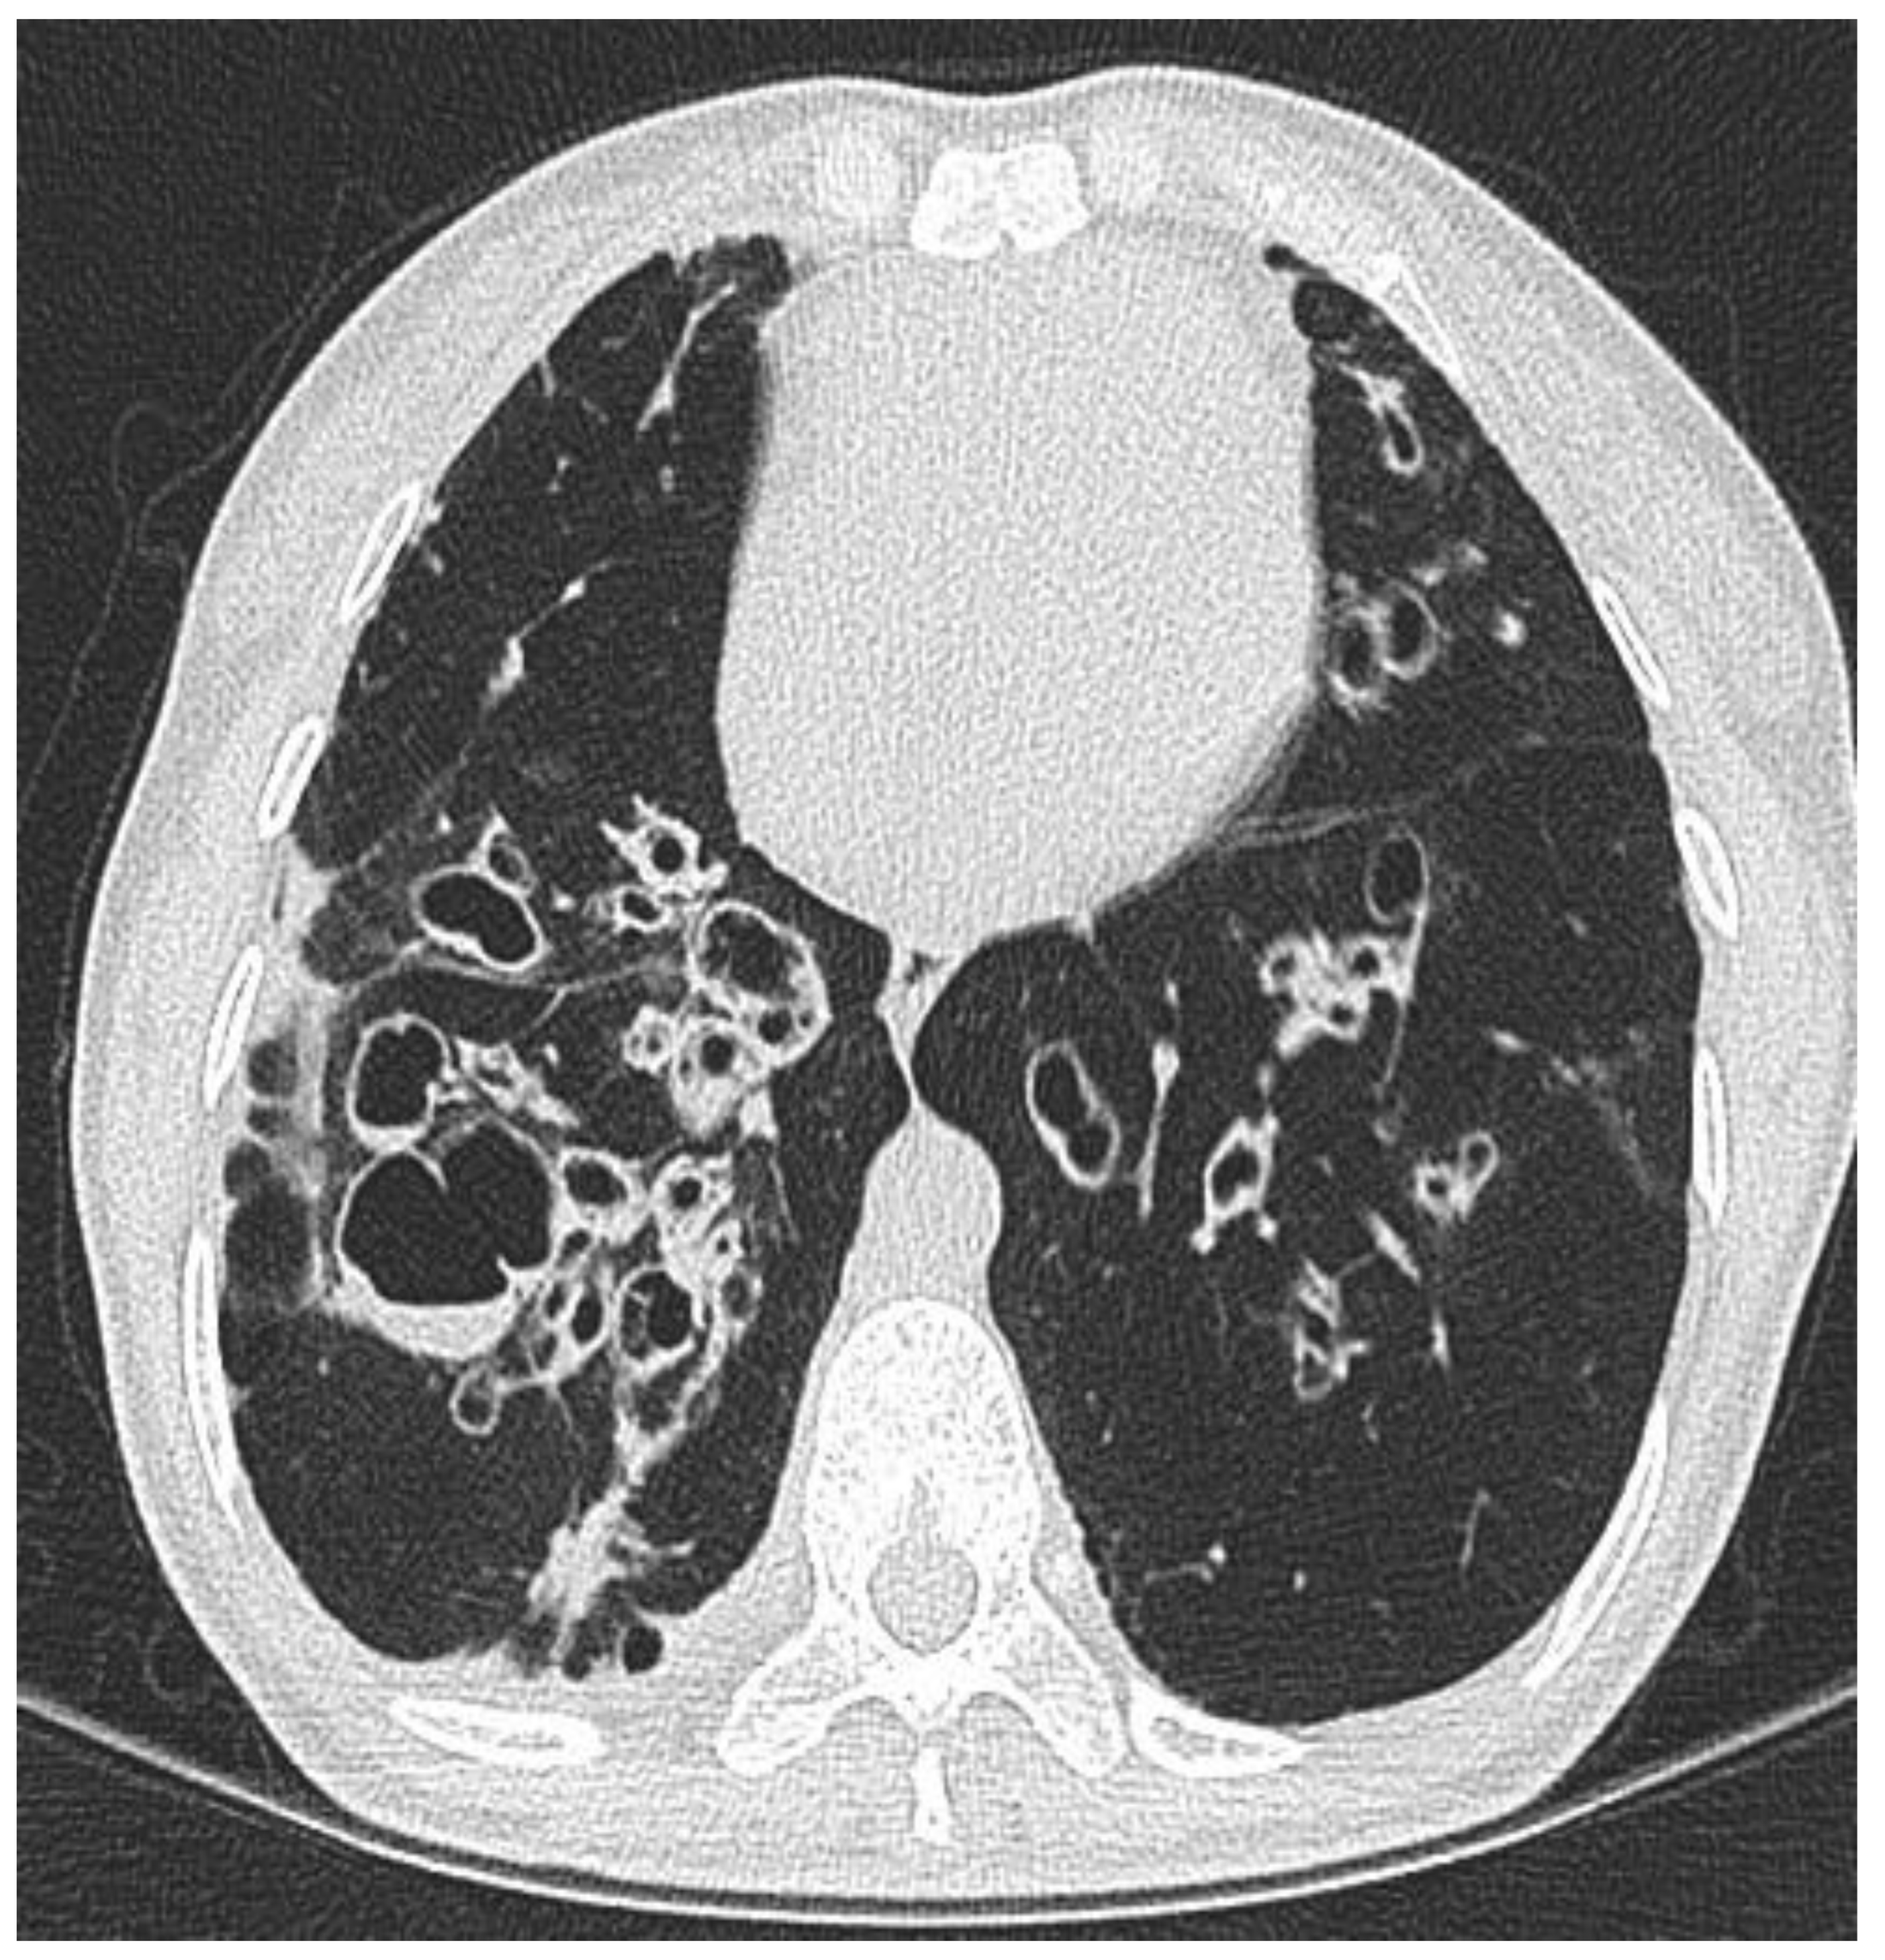

2.1. Clinical Phenotype by Radiology

- Juliusson, G.; Gudmundsson, G. Diagnostic imaging in adult non-cystic fibrosis bronchiectasis. Breathe 2019, 15, 190–197. [Google Scholar] [CrossRef]